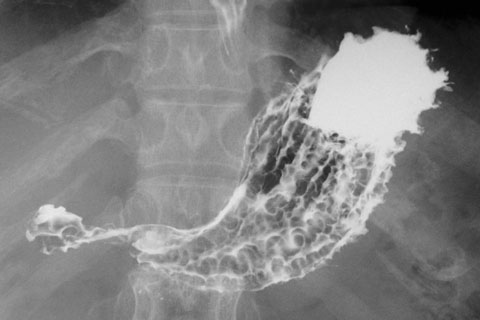

膵臓分裂は通常、磁気共鳴胆管膵管造影法(磁気MRCP)または内視鏡的逆行性胆管膵管造影法(ERCP)を使用して診断されます。

これらの方法では体内をスキャンし、医師は融合した 1 つの膵管ではなく 2 つの別々の膵管の存在を探します。

ERCP はカメラと X 線検査で、先端に小さなカメラを備えた柔軟なチューブが口から胃と小腸の上部に挿入されます。

膵臓系の X 線撮影を行う前に、医師は X 線に映る特別な色素を注射します。手続きには通常15分から90分かかります。